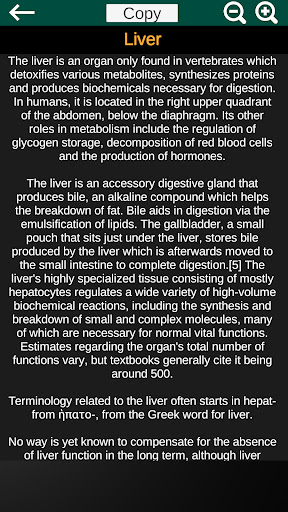

* Deskripsi masing-masing organ.